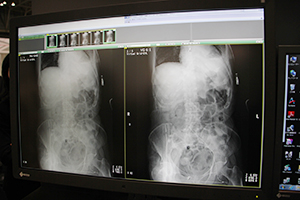

DRでのグリッドレス撮影を可能にする画像処理ソフトウエアVirtual Grid。腹部画像でも散乱線推定画像の差分処理で高コントラストを実現